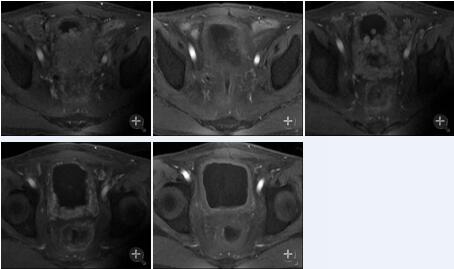

患者男性,63岁。

直肠癌术后Ⅳ期,膀胱、盆腹腔及骨多发转移。

治疗后一个疗程后复查,膀胱及直肠病灶明显缩小,肛周复发灶较前缩小,血尿症状消失,疼痛症状消失,其他症状显著缓解。